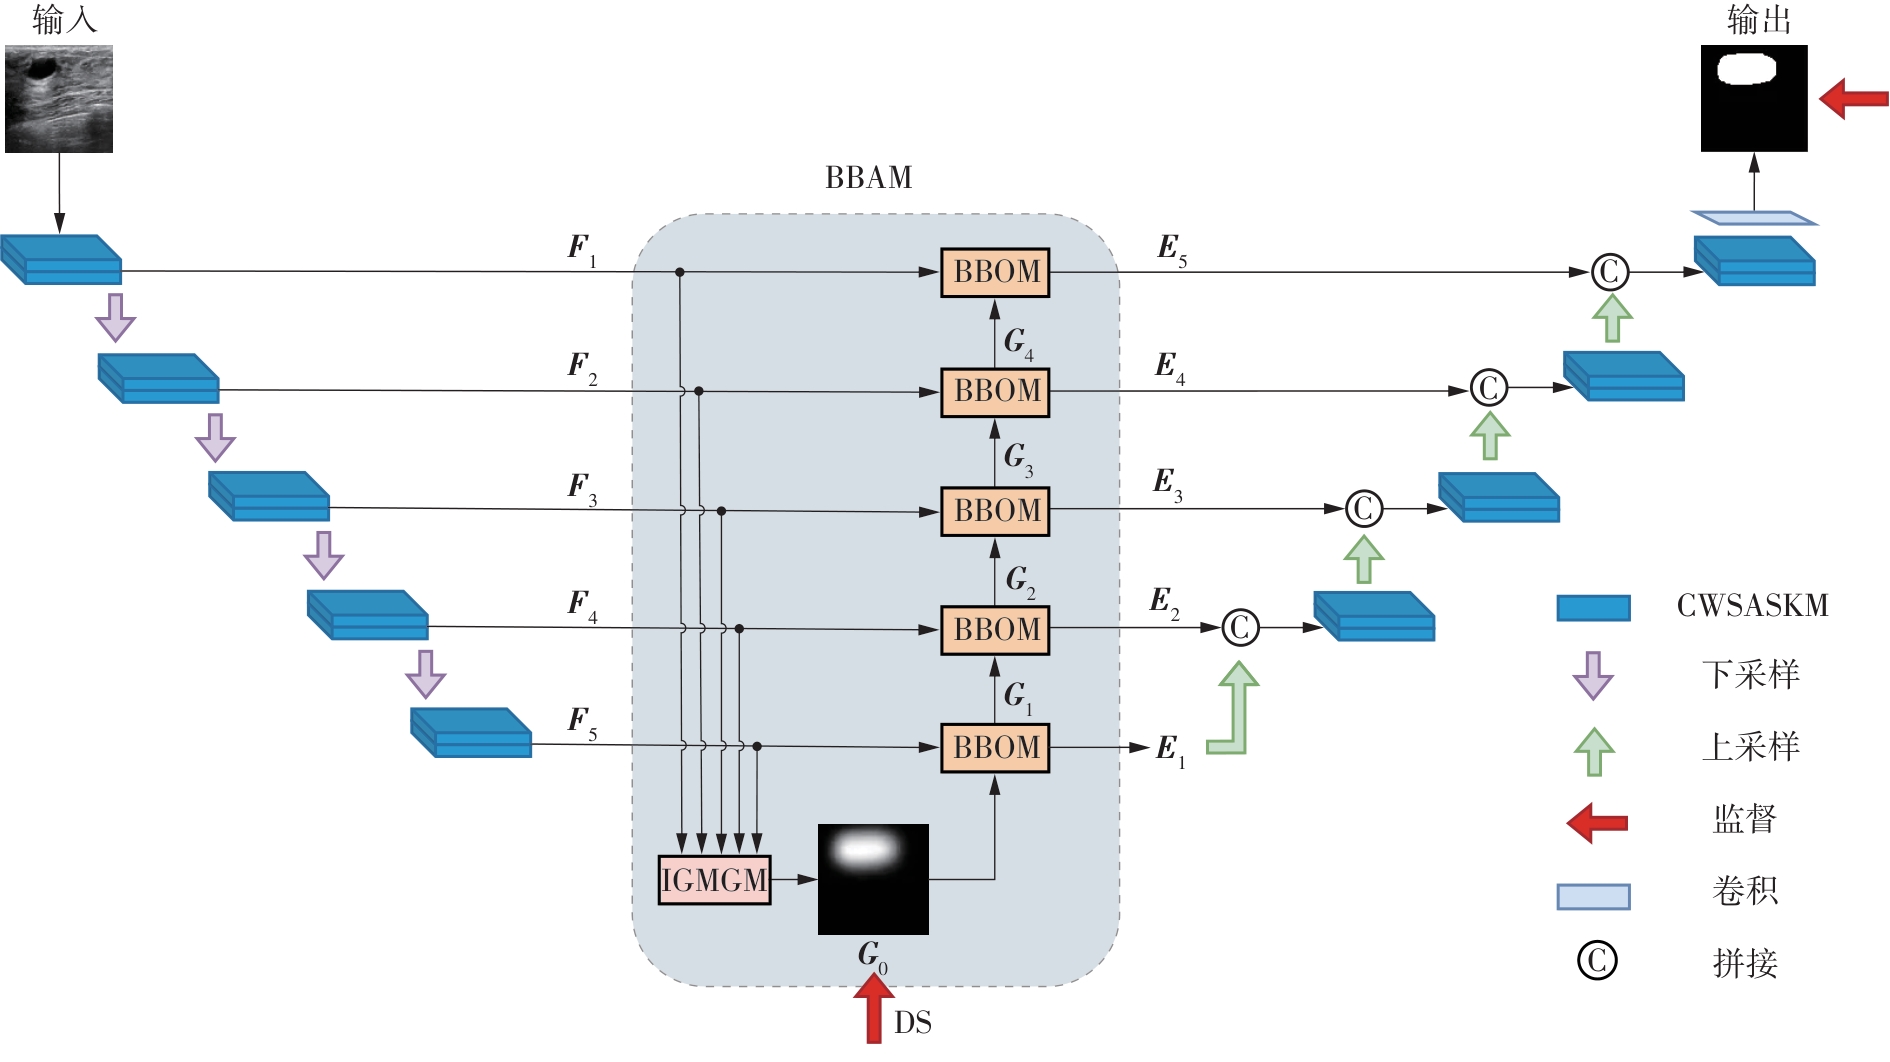

乳腺癌是全球女性最常见的恶性肿瘤之一,准确的病变分割对于乳腺癌的早期诊断与治疗具有重要意义。然而,由于病变形态的多样性以及超声成像机制的复杂性,现有基于深度学习的乳腺超声图像病变分割方法在分割准确性方面仍面临巨大挑战。为进一步提升乳腺超声图像中病变区域的分割精度,该文基于经典U-Net架构,提出了一种新型乳腺超声图像病变分割网络(CWSASKM-BBAM-Net)。首先,在网络中引入逐通道空间自适应选择核卷积模块(CWSASKM),根据不同通道的语义特征为每个空间位置自适应选择感受野大小,以增强多尺度信息的建模能力;然后,引入双向边界感知机制(BBAM),通过融合正向与反向注意力,对目标显著区域及其边界进行协同建模,同时逐步提升对非显著区域与病变区域的区分能力,以进一步强化边界信息的表达;最后,在3组公开乳腺超声图像数据集(BUSI、UDIAT和STU)上开展分割实验。结果表明:该方法在数据集BUSI上的杰卡德指数、精确率、召回率和Dice相似系数分别为71.97%、82.85%、81.40%和80.44%,较次优方法分别提升1.69、1.05、1.28和1.84个百分点;在数据集UDIAT上,这4项指标分别达到78.14%、88.31%、86.73%和86.10%,较次优方法分别提升了2.75、2.04、0.56和2.01个百分点;在外部数据集STU上,该方法也取得了优于其他方法的整体表现。实验结果表明,CWSASKM-BBAM-Net在乳腺超声图像分割任务中展现出更优的整体性能。